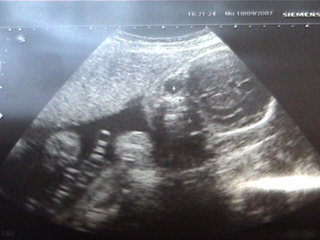

Holnap írok, addig néhány kép:

Kép 2D-n

Kép A bizonyíték - tényleg fiú

Kép A gondolkodó

Kép A talpával is takarta magát

Kép Manó alszik